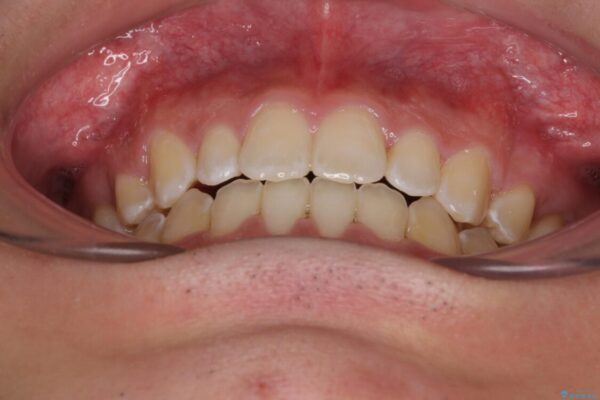

受け口傾向の咬み合わせと口元の突出感を気にして来院された患者様です。

受け口傾向特有の狭い上顎歯列であったため、歯列の拡大を補助装置で行い、下顎歯列全体を後方に移動させることとしました。

治療前

• 口元の突出感を改善 受け口傾向の咬み合わせの抜歯矯正 治療前画像